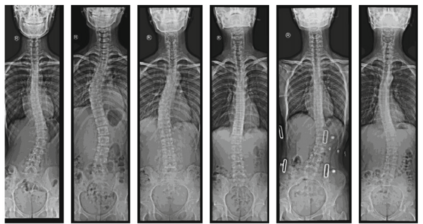

Scoliosis is a sideways curvature of the spine that most often is diagnosed among young teenagers. It dramatically affects the quality of life, which can cause complications from heart and lung injuries in severe cases. The current gold standard to detect and estimate scoliosis is to manually examine the spinal anterior-posterior X-ray images. This process is time-consuming, observer-dependent, and has high inter-rater variability. Consequently, there has been increasing interest in automatic scoliosis estimation from spinal X-ray images, and the development of deep learning has shown amazing achievements in automatic spinal curvature estimation. The main target of this thesis is to review the fundamental concepts of deep learning, analyze how deep learning is applied to detect spinal curvature, explore the practical deep learning-based models that have been employed. It aims to improve the accuracy of scoliosis detection and implement the most successful one for automated Cobb angle prediction. Keywords: Scoliosis Detection, Spinal Curvature Estimation, Deep Learning. i